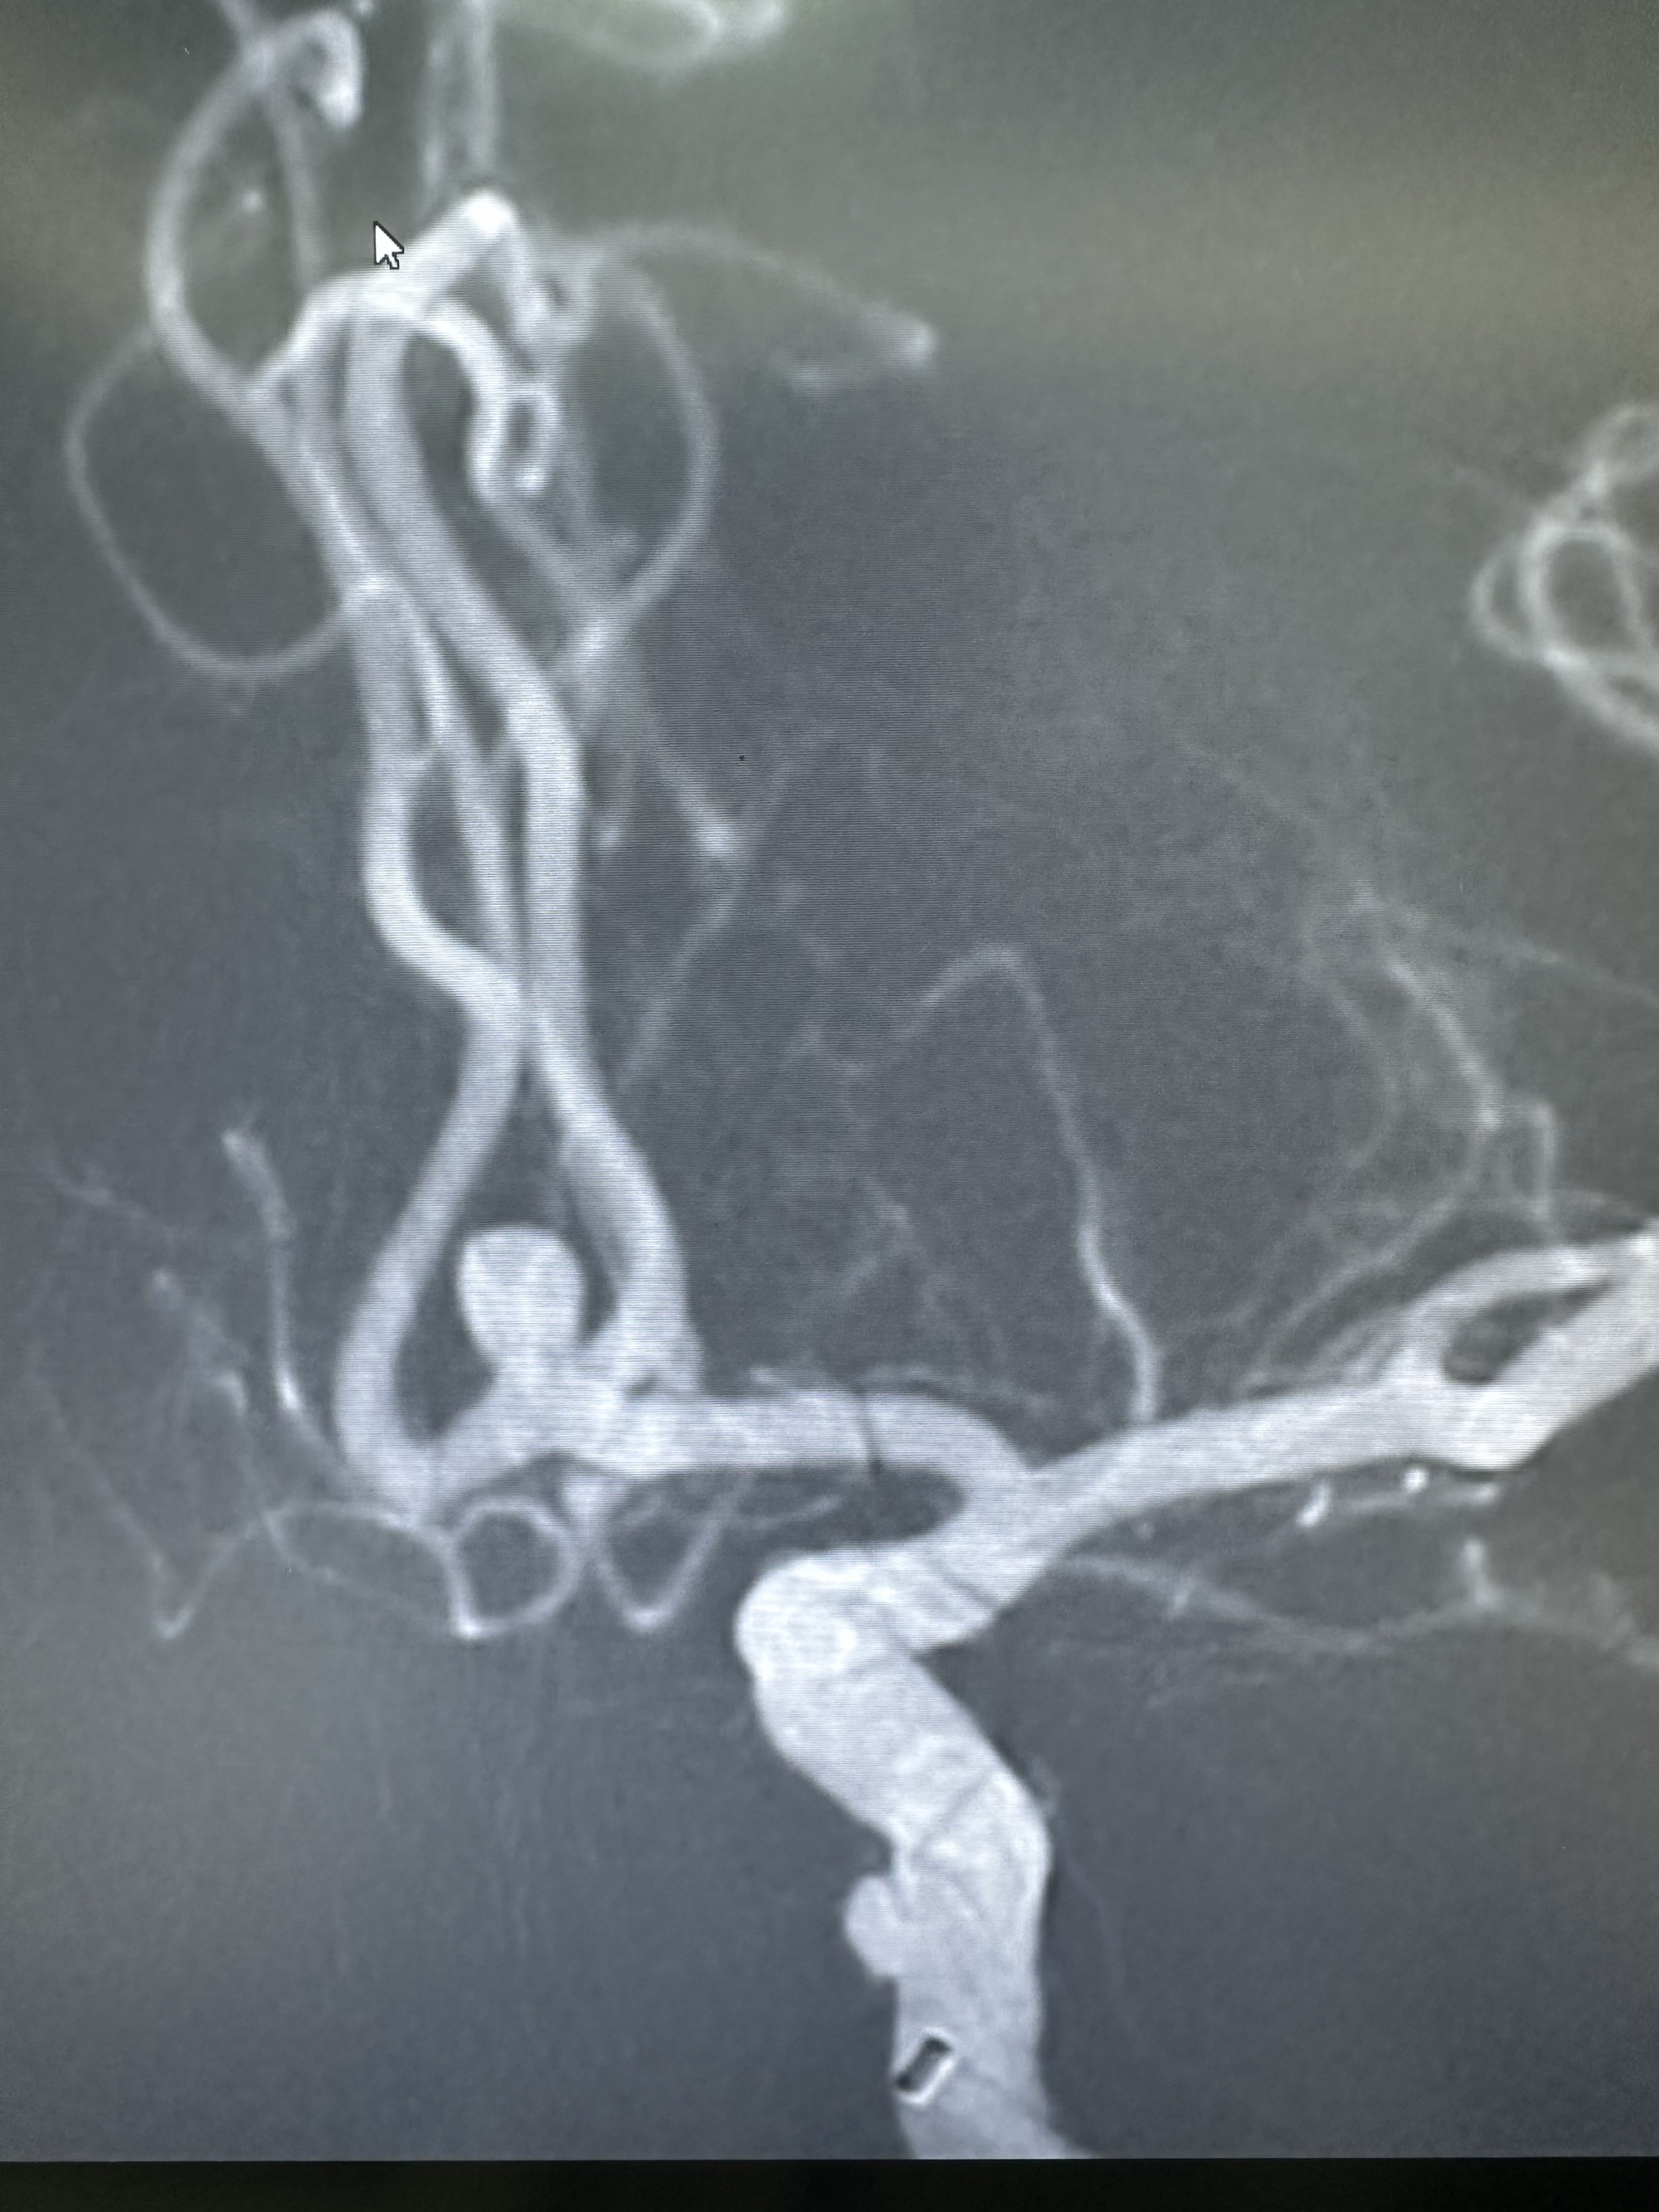

3D造影

另外一个角度